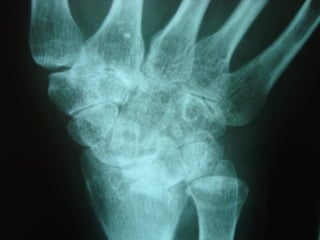

Achados radiográficosAchados radiográficos

 Osteopenia peri-articularOsteopenia peri-articular

 Diminuição do espaço articularDiminuição do espaço articular

 Presença de cisto e erosõesPresença de cisto e erosões

 Edema de partes molesEdema de partes moles

 Presença de deformidadesPresença de deformidades

1- osteopenia 2-erosões 3-sub-luxação